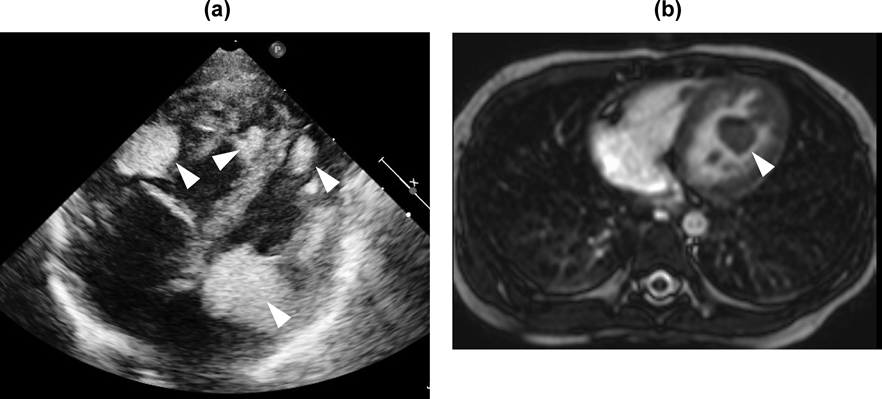

Table 1 shows the imaging characteristics of primary cardiac tumors in children. Cardiac rhabdomyomas are commonly multiple (in more than 60% of patients) and multiple rhabdomyomas are highly associated with TSC.5) Cardiac rhabdomyomas are located on either of the ventricles, especially on the left, with or without outflow obstruction. Echocardiography can detect rhabdomyomas as hyperechoic solid masses (Fig. 1a). CT provides anatomical information such as the myocardium contiguous with the tumors, or the nature of the tissues of the tumors themselves. This modality is helpful, as mentioned above, for comprehensive assessment of metastatic disease.6) Cardiac MRI shows isointense to myocardium on T1-weighted images and hyperintense on T2-weighted images (Fig. 1b).7) With contrast-enhanced imaging, cardiac rhabdomyomas appear as areas weakly enhanced. CT and cardiac MRI are non-invasive diagnostic tools. The imaging features from these modalities, although non-specific, are often used to characterize the mass further, eventually facilitating diagnoses and guiding treatments.6, 7) Histological assessment remains as a gold standard for confirmation of a pathological diagnosis.

Fig. 1 Cardiac rhabdomyoma on echocardiography and cardiac MRI

a) Echocardiographic features. Echocardiography shows multiple rhabdomyomas located in both ventricles as hyperechoic solid masses. Arrowheads show multiple rhabdomyomas. b) Cardiac MRI. Cardiac MRI shows solitary rhabdomyoma in the left ventricle as hyperintense mass on T2-weighted images. Arrowhead shows solitary rhabdomyoma in the left ventricle.